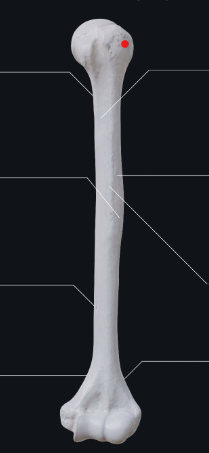

head

lesser tubercle

greater tubercle

surgical neck